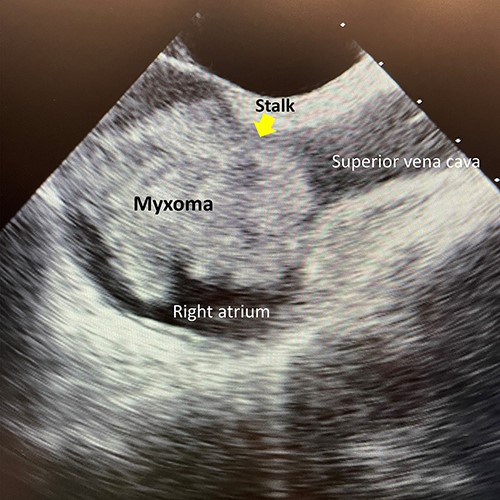

A 56-year-old woman without any past medical history complaining of dyspnea was consulted at our hospital. A contrast-enhanced computed tomography revealed a non-enhanced large mass in the right atrium and pulmonary embolism in the distal part of the left inferior pulmonary artery. Preoperative transesophageal echocardiography (TEE) showed the large highly mobile mass measuring 40 × 41-mm length in the right atrium. The mass attached to the interatrial septum near the ostium of superior vena cava and the diameter of the stalk was 8 mm (Fig. 1). The patient was hemodynamically stable and her saturation of pulse oximetry was 98% at room air.